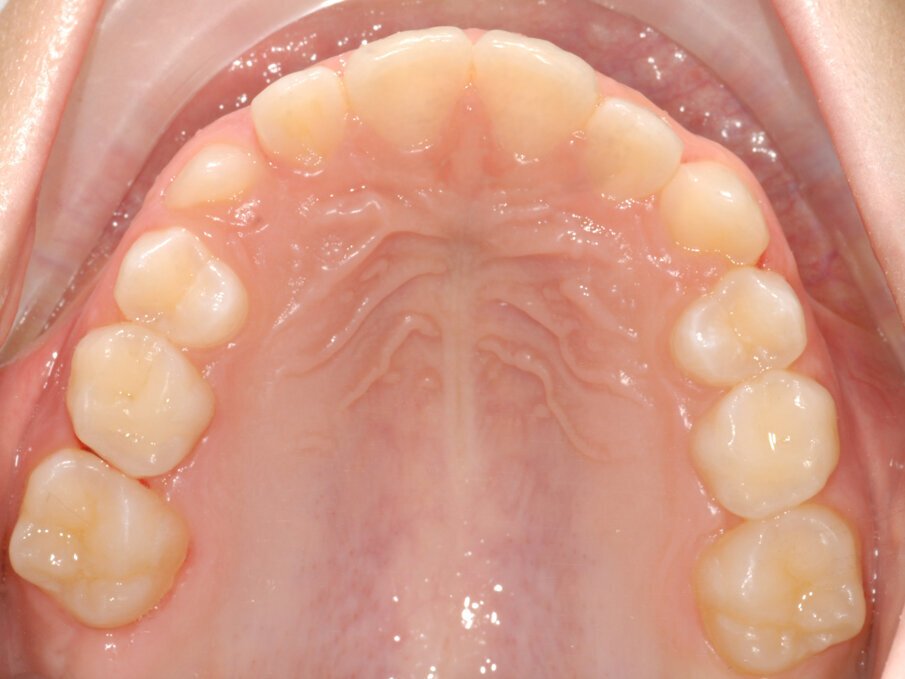

La piccola Sofia viene sottoposta a una prima visita ortodontica all’età di 8 anni, l’esame obiettivo (Figg. 1, 2) e l’ortopantomografia (Fig. 3) delle arcate dentarie evidenziano una mancanza di spazio per la corretta eruzione dei canini superiori (1.3-2.3).

Fig. 2_Vista occlusale iniziale.